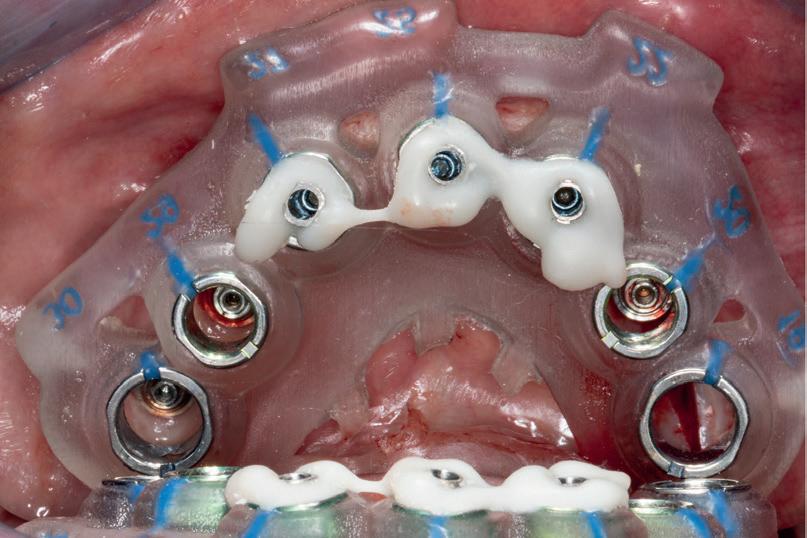

SITE AUGMENTATION Reconstituirea țesutului moale periimplantar și papilar în zona estetică

RECONSTITUIREA țesuturilor moi periimplantare. Scopul acestui raport de caz este de a demonstra procedurile chirurgicale utilizate pentru corectarea unui defect al țesuturilor moi periimplantare folosind țesutul moale interdentar în combinație cu tuberozitatea ca locație donatoare de țesut conjunctiv, utilizând o abordare prin tunelizare într-o zonă estetică.